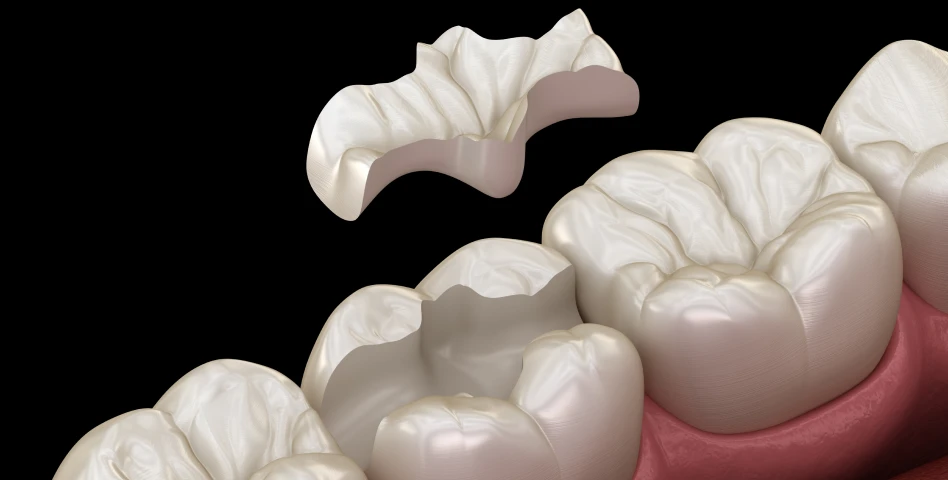

C’est une racine artificielle en titane placée dans l’os de la mâchoire pour remplacer une dent manquante.